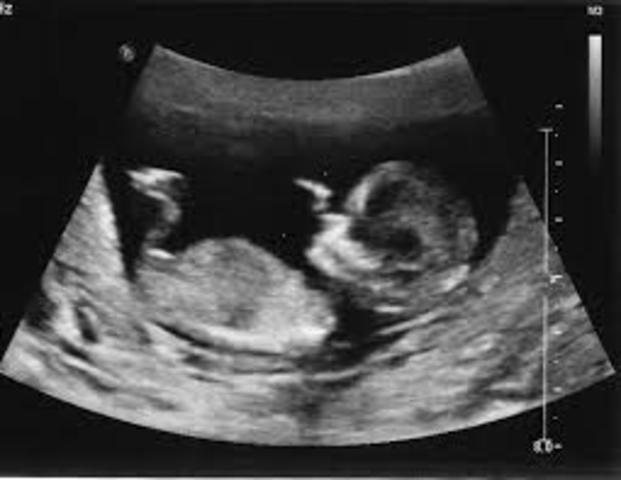

• time for the ultra sound

time for the ultra sound

during ultra sound the doctor will make sure placenta is healthy and attached normally and you will know your baby is growing properly.